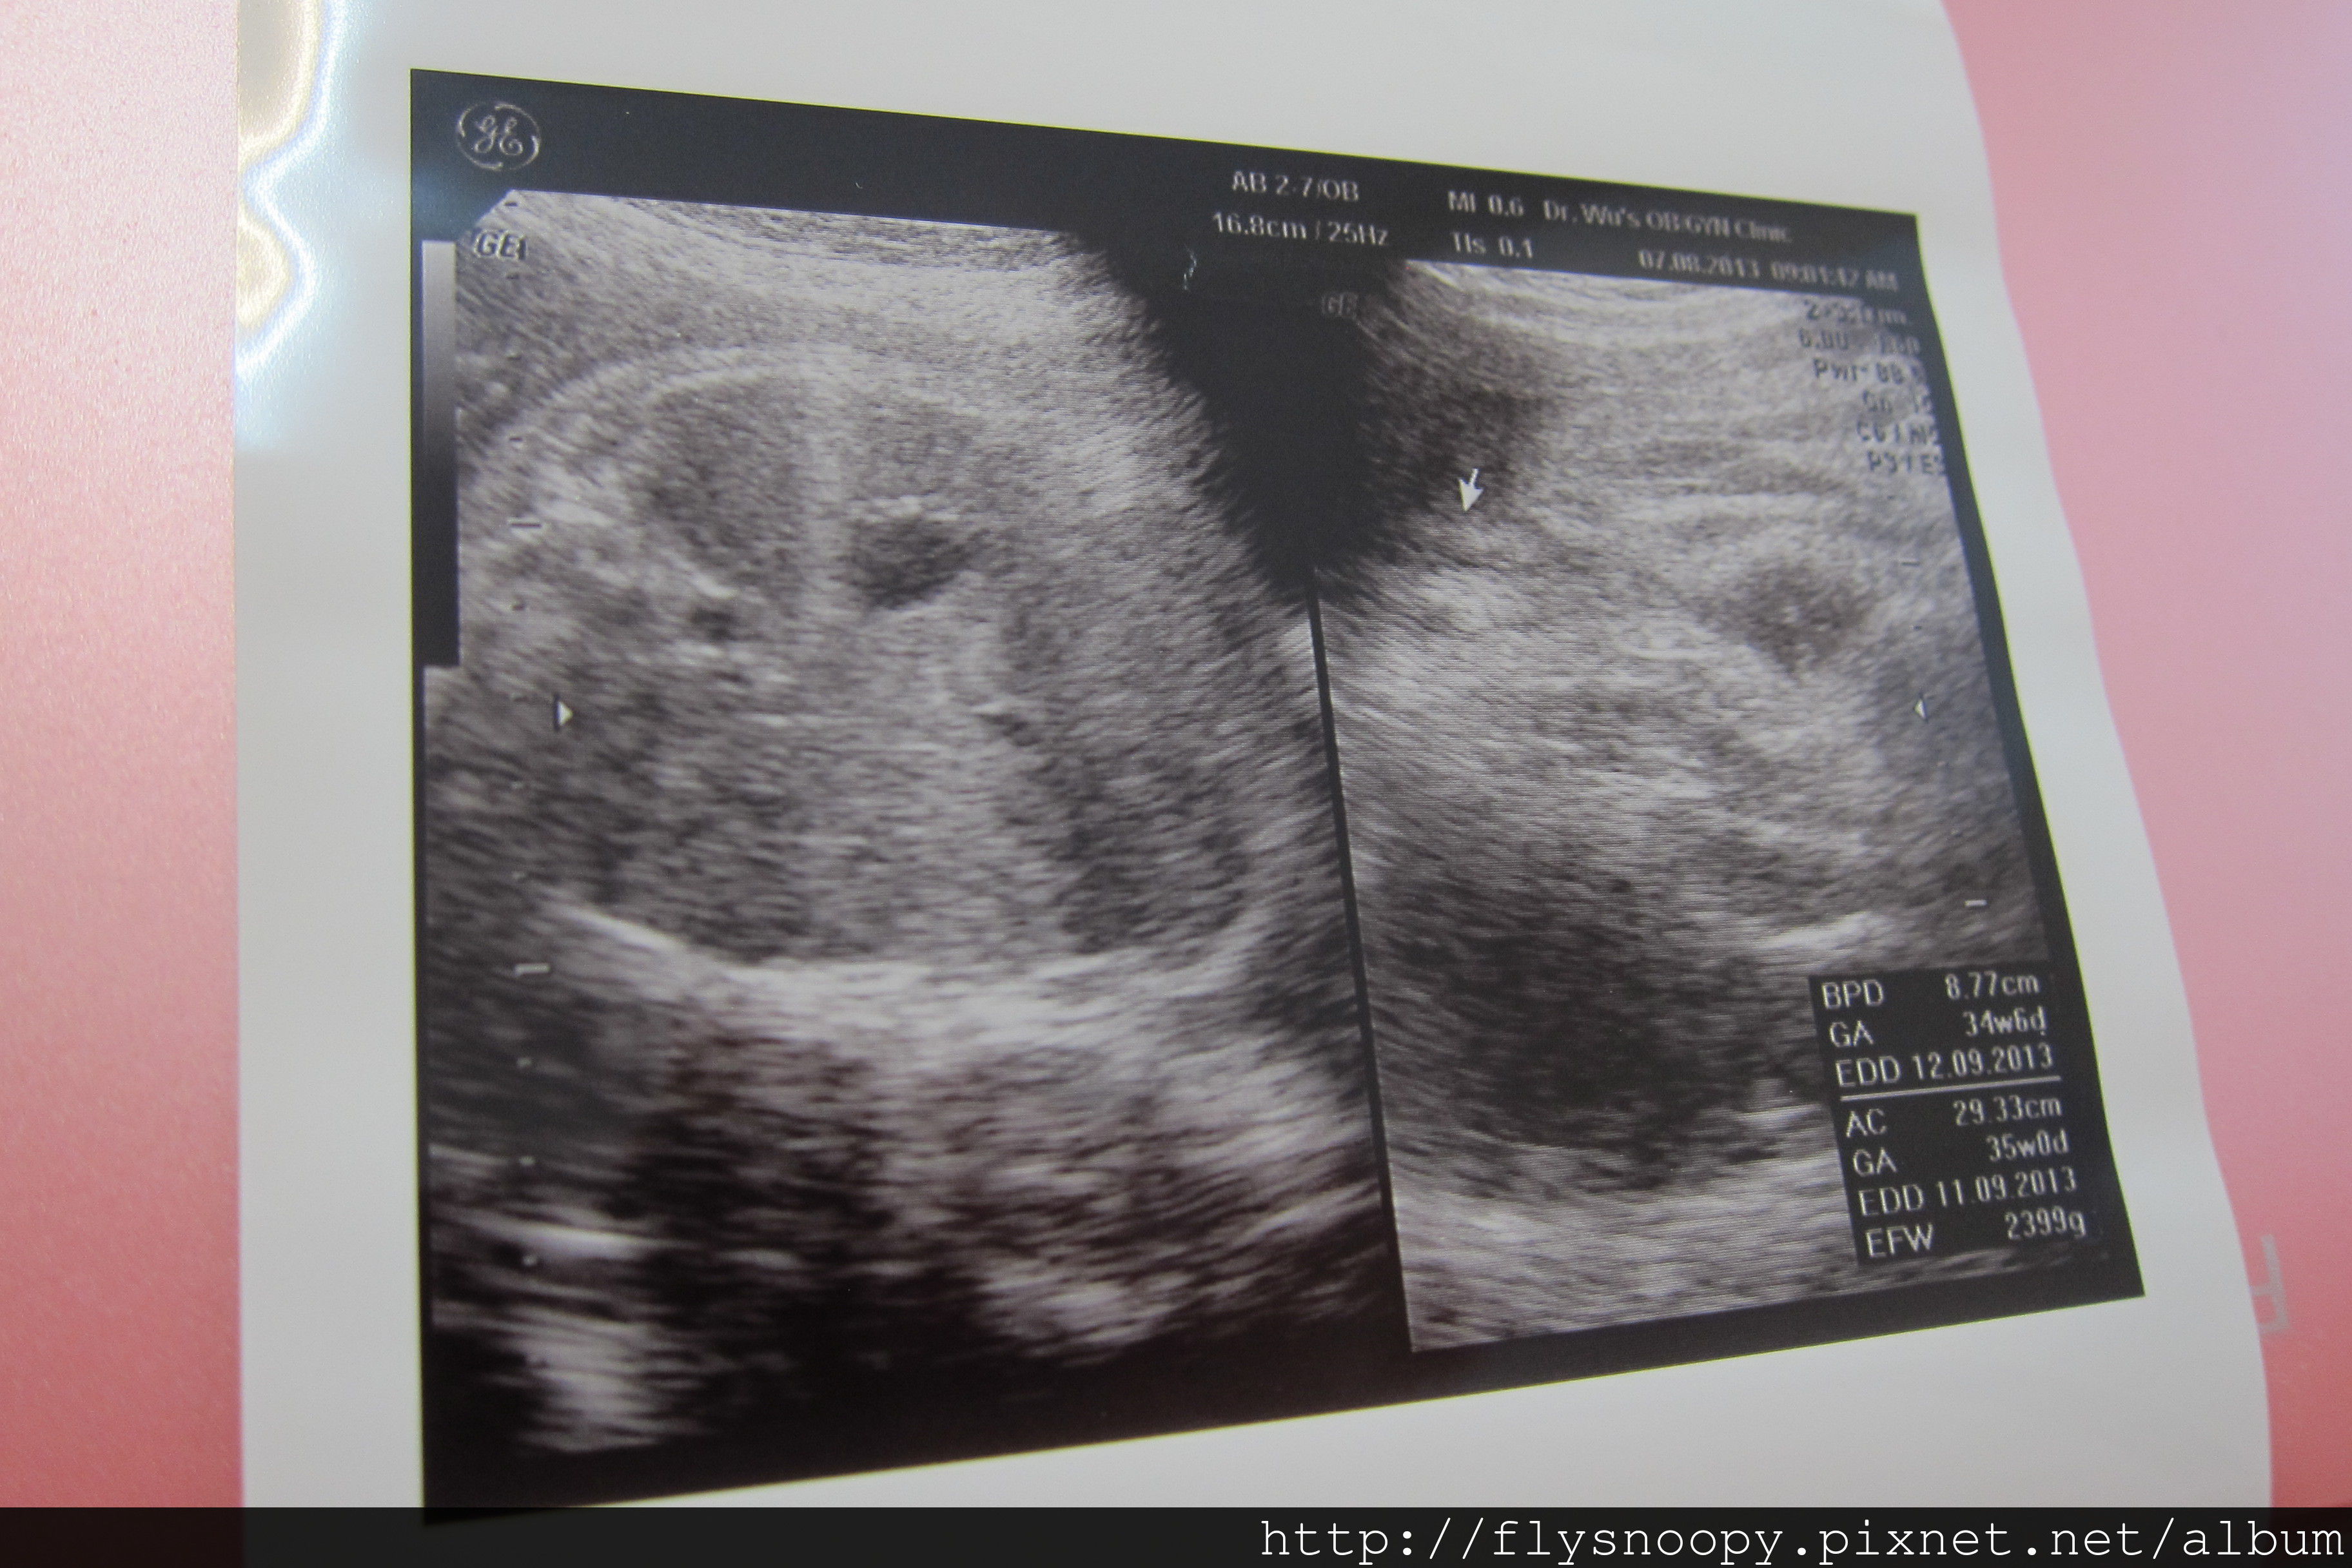

8/7第9次產檢

第九次產檢記錄

體重:64.7

血壓:119/72

尿糖、尿蛋白:正常

EFW:2399